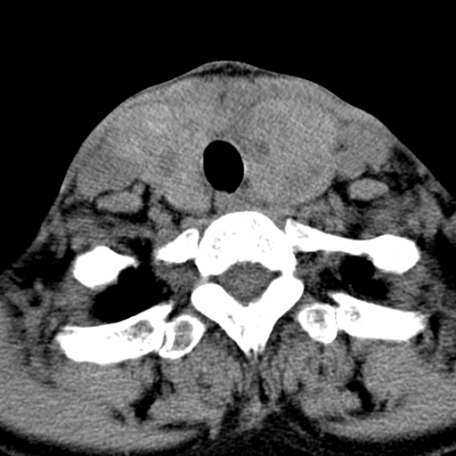

标题: CT24010:患者女56岁双侧甲状腺摘除术后一月复查,患者现感 [打印本页]

标题: CT24010:患者女56岁双侧甲状腺摘除术后一月复查,患者现感

甲状腺术后复发,现在甲状腺区域仍有密度不均匀之软组织密度影。

甲状腺区域密度不均匀密度影,应该是术后改变,要鉴别是否复发,建议增强检查。

“甲状腺摘除术后一月复查”,有病理吗?考虑术后复发,可能是恶性,颌下及左侧颈部淋巴结有肿大。

考虑术后复发,并颈部淋巴结肿大。请结合临床。

双侧甲状腺肿大,周围结构不清,术后复发时间有点短,考虑出血并感染。